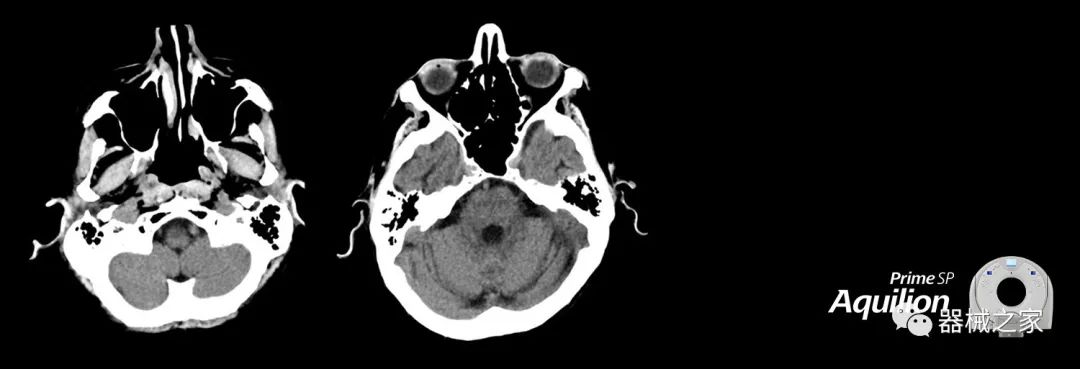

在以患者為中心的放射腫瘤學(xué)領(lǐng)域,計(jì)算機(jī)斷層掃描(CT)的可訪問(wèn)性,可重復(fù)性和靈活性至關(guān)重要。為了建立這些價(jià)值,佳能醫(yī)療系統(tǒng)美國(guó)公司現(xiàn)在正在擴(kuò)大其放射腫瘤學(xué)CT模擬產(chǎn)品,包括Aquilion Prime SP和Aquilion Lightning 80高級(jí)CT系統(tǒng)。除了Aquilion LB之外,Aquilion Prime SP和Aquilion Lightning 80現(xiàn)在還包括放射治療(RT)選項(xiàng),可為腫瘤學(xué)規(guī)劃提供高質(zhì)量的CT成像和精密工具。

擴(kuò)展視野(EFOV)可以看到更多的解剖結(jié)構(gòu)。Aquilion LB采用85 cm EFOV,而Aquilion Prime SP和Aquilion Lightning 70采用70 cm EFOV。

兩個(gè)CT系統(tǒng)均采用0.5 mm x 80排PUREViSION探測(cè)器技術(shù)(可配置并從80-160現(xiàn)場(chǎng)升級(jí)),78 cm孔徑,50 cm視野,AIDR(自適應(yīng)迭代劑量減少)3-D和SEMAR(單個(gè))能量金屬神器減少)技術(shù)。

Aquilion LB專為滿足腫瘤學(xué)挑戰(zhàn)而設(shè)計(jì),同時(shí)優(yōu)先考慮患者護(hù)理。Aquilion LB的內(nèi)徑為90 cm,能夠幫助復(fù)雜的患者設(shè)置并提高患者的舒適度。CT模擬定位可以輕松鏡像放射治療定位,更加自信。該系統(tǒng)采用0.5 mm x 16排(32層)PUREViSION探測(cè)器技術(shù),70 cm視野,AIDR 3D和SEMAR技術(shù)。